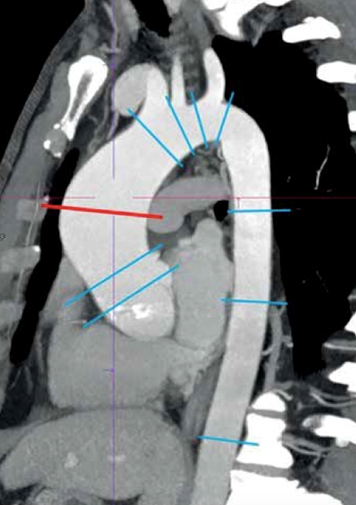

Комментарии. Измерения диаметра аорты следует проводить перпендикулярно оси аорты в определенных точках (Рисунок 3), а также выполнять дополнительные замеры в местах каких-либо аномалий (локальные расширения, изъязвления, гематомы). Крайними точками при измерении диаметра аорты должны быть внешние стороны ее стенки, то есть толщина стенки аорты при измерении ее диаметра должна учитываться. При выраженном утолщении аортальной стенки (5 мм и более), а также в случае наличия интрамуральной гематомы целесообразно отдельно измерять диаметр внутреннего просвета грудной аорты, толщину ее стенки, распространенность утолщения (гематомы), и отражать эти сведения в заключении [42].

Рисунок 3. Особенности выполнения измерений аорты при эхокардиографии и рентгеновской компьютерно-томографической ангиографии

С МРА и КТА аорты†

(A) Методика измерений «между внешними краями», используемая при эхокардиографии, слева направо: измерение максимального диаметра на уровне корня аорты (синусов Вальсальвы), синотубулярного соединения и тубулярной части восходящей аорты. (Б) Измерения диаметров корня аорты «синус-комиссура» и «синус-синус» в ходе КТА или МРА. (С) Стандартные зоны измерений грудной аорты при анализе КТА или МРА. Источник: Боргер и соавторы [46], авторское право 2018 года; публикуется с согласия Elsevier, Inc. КТА –компьютерно-томографическая ангиография; МРА – магнитно-резонансная ангиография. *Между внешними краями. †Между внутренними стенками.

Рекомендуется у пациентов с подтвержденным или предполагаемым поражением грудной аорты при выполнении КТА или МРА аорты измерять диаметры на уровне синусов Вальсальвы, синотубулярного соединения и тубулярной части восходящего отдела аорты между ее внешними сторонами с использованием ЭКГ-синхронизированной методики (Таблица 3) [43].

Комментарии. Использование техники ЭКГ-синхронизации при проведении КТА уменьшает артефакты движения корня и восходящего отдела аорты [47], значительно повышая этим точность измерений и достоверность диагностики. При КТА и МРА грудной аорты диаметр корня аорты можно измерять от комиссуры до стенки противоположного синуса или от стенки одного синуса до стенки другого (Рисунок 4) [48]. Измерение от синуса до синуса и между внутренними краями на КТА грудной аорты и МРА грудной аорты продемонстрировало хорошую корреляцию с результатами эхокардиографии при измерении корня и восходящего сегмента аорты [43]. Измерение диаметра протеза аорты (например, имплантированного хирургическим путем синтетического сосудистого протеза либо стент-графта для транскатетерной изоляции патологии грудной аорты) может также включать проведение замеров между внутренними краями, что позволяет определить функциональный просвет и может быть использовано при планировании дополнительных лечебных мероприятий.

Рисунок 4. Стандартные зоны измерений диаметров грудной аорты (адаптировано из Скрипник А.Ю. и соавт., 2019 [49]).